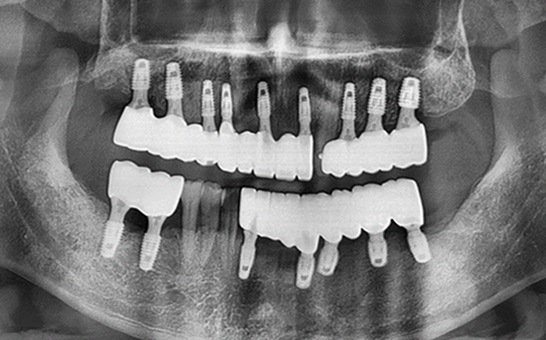

CASE 01 김** / 60대

전악임플란트

치료 시작 전 촬영 2024.01.24 | 치료 완료 후 촬영 2024.12.26

1 예후불량 치아 발치

2 발치 후 즉시 임플란트 식립 및 뼈이식

3 고정성 보철물로 수복 후 일상 회복